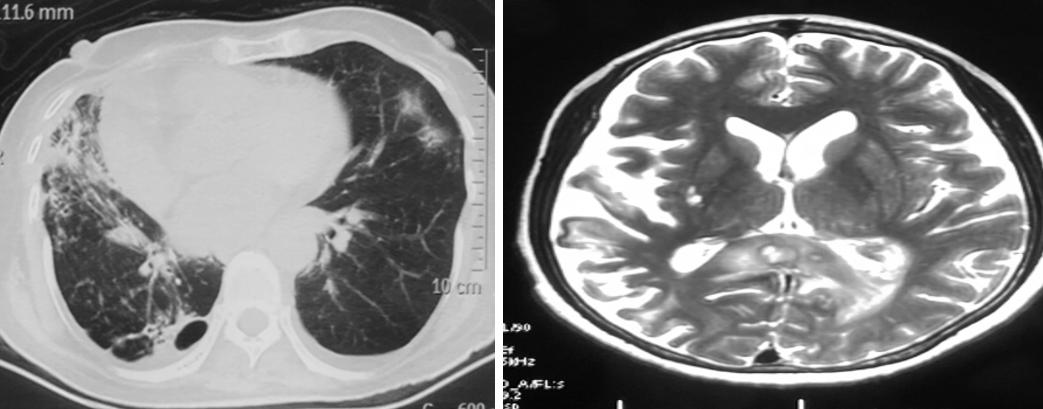

影像可见患者右下肺有较大的实变:

胸水是血性的,我们下了决心去穿刺,肺穿刺组织培养48小时发现根毛霉,病理也看到了丝状真菌:

21岁男大学生,肺部阴影3年余,头晕2月。早期呈现为肺部感染,未拿到病原学证据,随着病情逐渐进展,住院时发现血嗜酸性粒细胞、总IgE特别高,于是怀疑是高IgE综合症。

2017.9:体检发现肺部空洞(PPD阳性,TB-DOT阳性,曲霉菌抗体阳性)→抗细菌、抗真菌、抗结核吸收欠佳。

2018.3:气管镜(刷片、灌洗及透壁活检病理均未见异常, BALF病原学阴性),透壁活检后出现气液平→肺脓肿,脓胸→胸水培养提示具核梭杆菌;IgE:2265kU/L,烟曲霉IgE:2.73,抗真菌、细菌治疗。

2020.10:头晕,伴有左侧肢体麻木2个月;头颅核磁:肿块伴环形强化;PET-CT:颅内,肺部,皮下,腹腔、左侧股骨颈;代谢活性增高多发结节灶;血嗜酸性粒细胞3.6*10^9/L,总IgE大于5000kU/L。